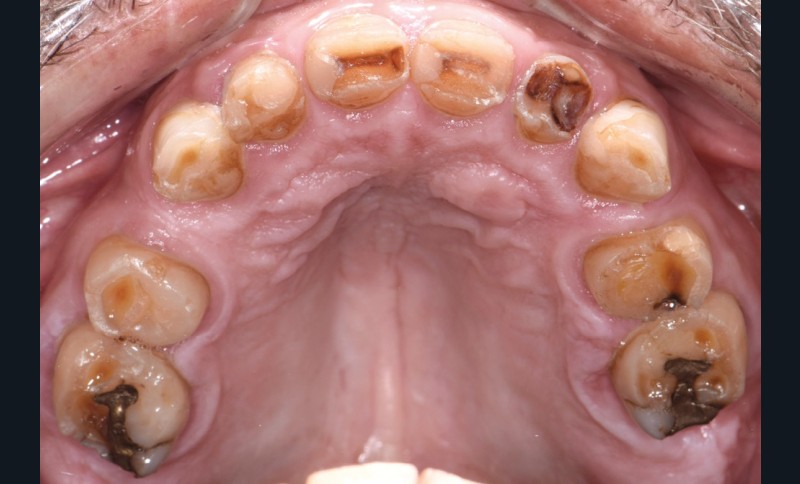

Au vu du contexte para-fonctionnel et de l’étendue de la perte tissulaire, des coiffes périphériques minimalement invasives ont été choisies afin de restaurer l’esthétique et la fonction. Actuellement, aucun consensus n’est fait sur le choix du matériau d’infrastructure à privilégier. Les matériaux hybrides usinables présentent des propriétés mécaniques, physiques et biologiques intéressantes en contexte d’usure sévère (e.g., module d’élasticité, résistance à la propagation de fêlures, facilité de réintervention). Une réhabilitation globale avec remontée de dimension verticale d’occlusion (DVO) par l’intermédiaire de coiffes composites renforcés en nano-céramiques est décrite.